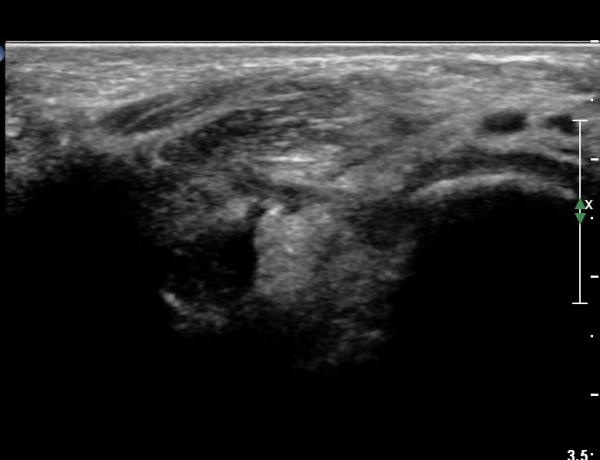

¹ß¸ñ °üÀý Á¾´Ü¸é°Ë»ç¿¡¼­ °æ¹ÌÇÑ °üÀý³» ºÎÁ¾À» º¸ÀÓ(»çÁø 1).

Àü°ÅºñÀδë Á¾´Ü¸é°Ë»ç¿¡¼­ Àü°Åºñ ÀδëÀÇ Àú¿¡ÄÚ ºÎÁ¶À» º¸ÀÓ(»çÁø 2).

Sinus tarsi Á¾´Ü¸é, Ⱦ´Ü¸é°Ë»ç¿¡¼­ sinus tarsi ³» ºÎÁ¾À» º¸ÀÓ(»çÁø 5, 6).